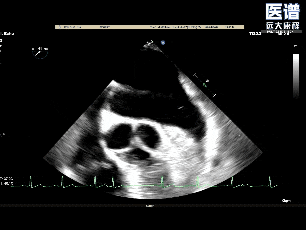

释放后3D评估(组织桥稳定)

释放后3D评估(反流少量)

术后平均压差为3mmHg

术中完成房间隔穿刺后,将可操控导引导管(SGC)及二尖瓣夹输送系统成功送入左心房。随后将瓣膜夹调整至二尖瓣上并逐步移至病变区域,经轴向调整后,夹合器于A1/P1交界区顺利捕获瓣叶并完成首次夹合,此时超声提示存在少量反流;为达到更优的治疗效果,王建安院士及刘先宝教授决定微调位置,打开夹合器调整轴向后,重新捕获瓣叶以夹合瓣叶并成功释放,最终有效解决了反流及脱垂问题。释放后食道超声评估仅存在少量反流,平均跨瓣压3mmHg,圆满完成手术。